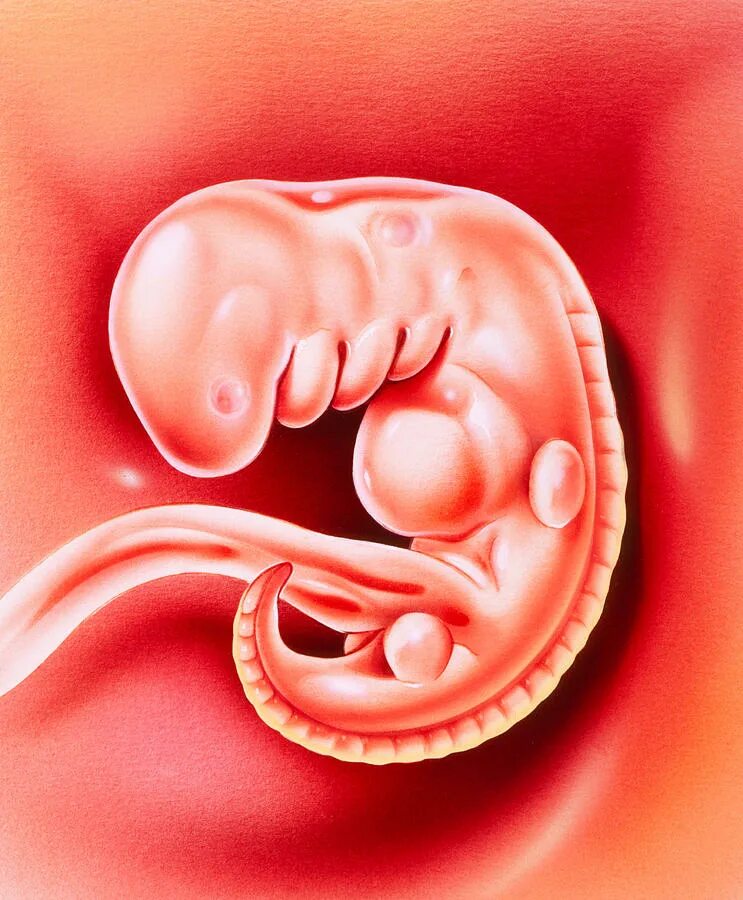

Куда девается эмбрион